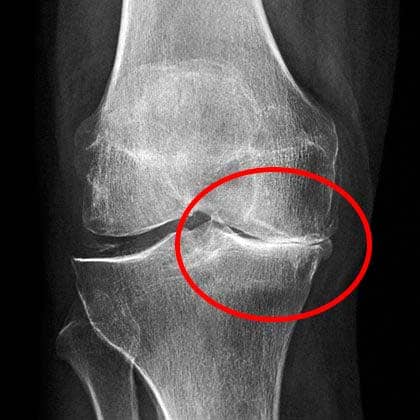

หมอดูฟิล์ม X-ray นานหน่อย แล้วบอกว่าฉันควรหลีกเลี่ยงการยกของหนักหรือทำงานหนัก ไม่ควรยกของหนักเกิน 2 กิโลกรัม!